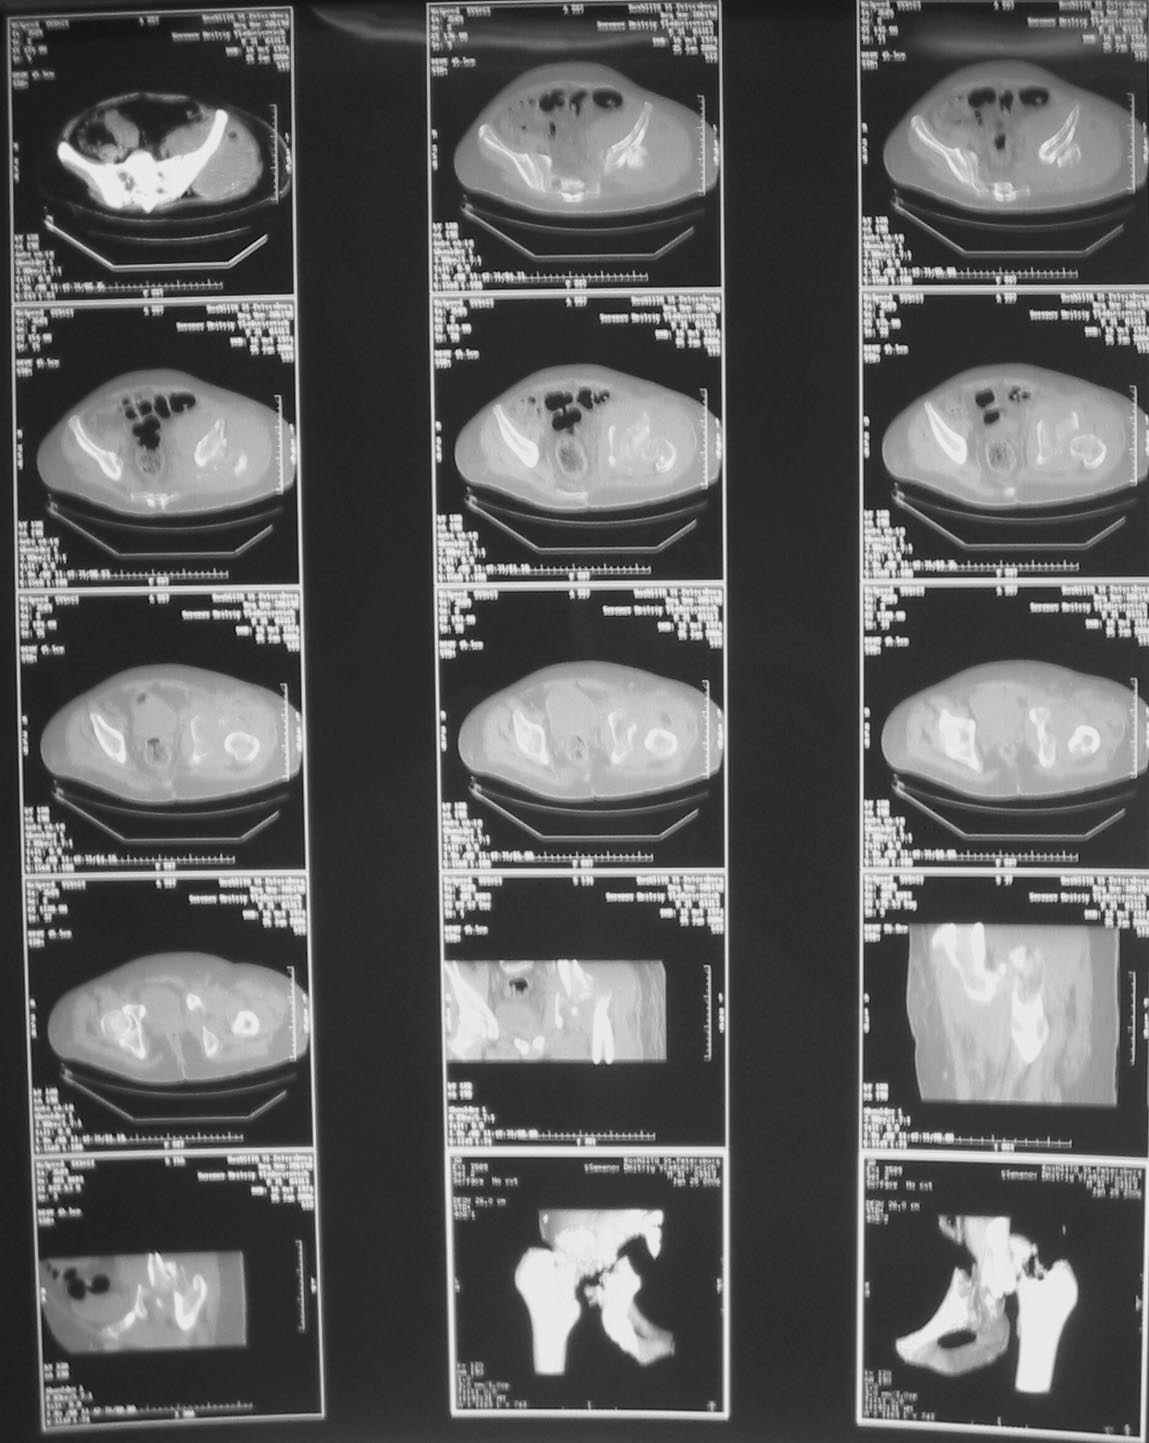

Дорогие коллеги, Поступил пациент, 5 месяцев, как сломался.

Поступил для эндопротезирования, но наши корифеи засомневались, не собрать ли сначала таз. Есть ли смысл собирать аппаратом закрыто?